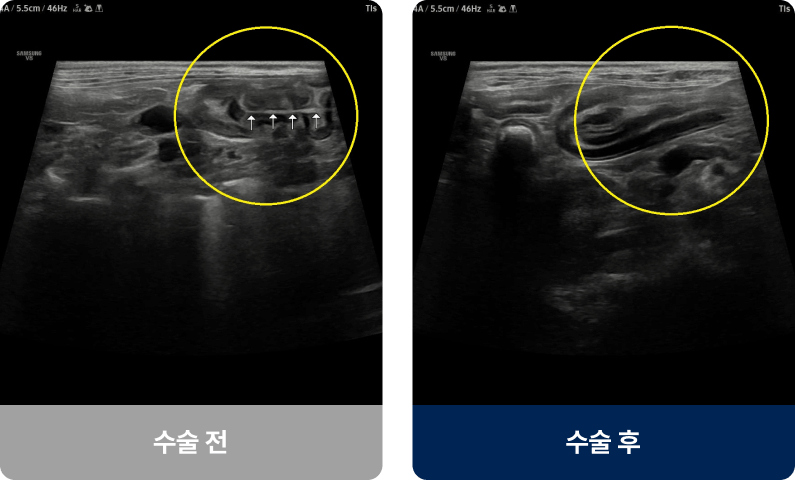

간에서 만든 담즙을 담아주는 작은 주머니인 담낭 안에 끈적한 점액이 과도하게 축적되는 상태로, 담즙이 제대로 배출되지 못하고 담낭 벽이 늘어나거나 터질 위험이 있습니다. 중년 이상의 강아지에게 발병률이 높으며, 식욕 저하·구토· 황달 증상을 보입니다.

외과적 치료법(수술적 치료)

담낭절제술

• 개복 또는 복강경을 통해 담낭 전체를 제거

• 담즙은 간에서 직접 장으로 흘러가므로, 담낭 제거 후에도 소화 기능

유지 가능